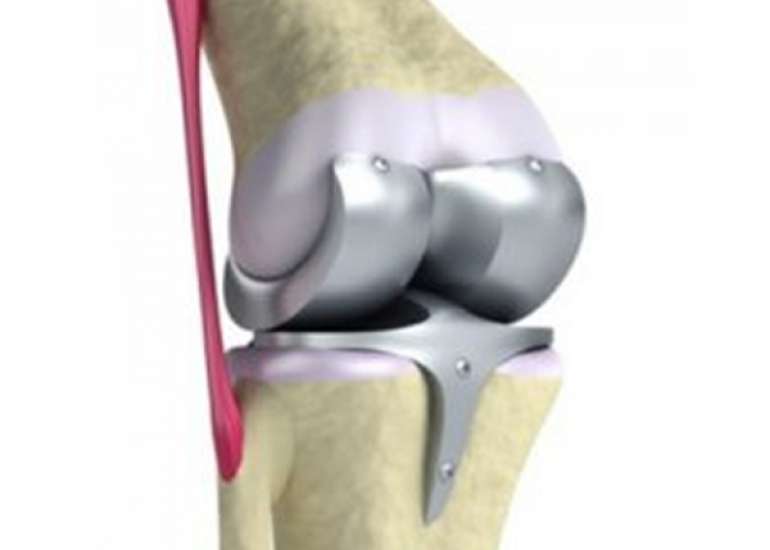

Director (Orthopaedics & Joint Replacement) & Head of Unit-1, Max Smart Super Speciality Hospital, Saket